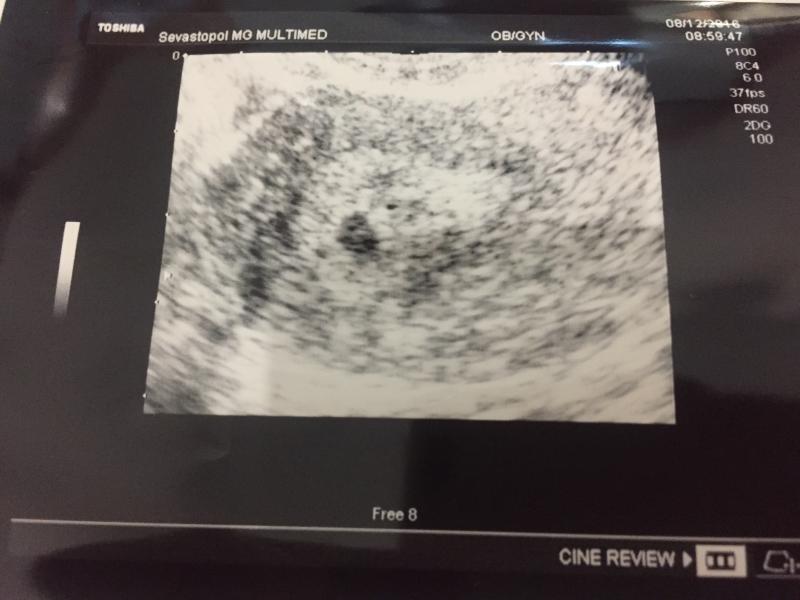

Привет рада познакомиться,тут фасолинка на УЗИ сказали перчинка😆